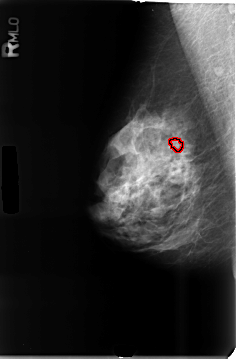

B_3464_1.RIGHT_MLO

RIGHT_MLO LINES 4656 PIXELS_PER_LINE 3064 BITS_PER_PIXEL 12 RESOLUTION 50 OVERLAY

FILE: B_3464_1.RIGHT_MLO.OVERLAY

TOTAL_ABNORMALITIES 1

ABNORMALITY 1

LESION_TYPE CALCIFICATION TYPE AMORPHOUS DISTRIBUTION CLUSTERED

ASSESSMENT 3

SUBTLETY 3

PATHOLOGY BENIGN

TOTAL_OUTLINES 1

BOUNDARY